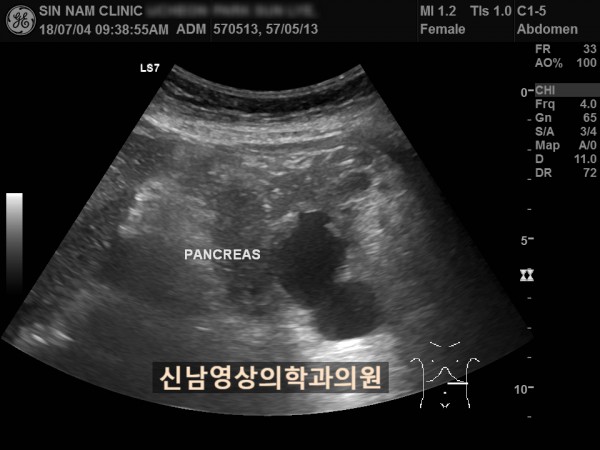

아래 환자분은 60대 여성분으로 식사만 하면 복통이 나타나서 내과에서 위 / 대장 내시경을 받으셨지만 정상으로 진단받았던 분으로 내과에서 복부 초음파검사를 했지만 이상 소견을 발견하지 못했던 분입니다.

초음파 검사는 영상의학과에서 받아야 한다는 주변 지인들의 말씀을 듣고, 본원을 내원해주셨어요.

복부 초음파 검사상 췌장꼬리(미부)에서 발생한 암으로 대장 장간막으로 전이가 되어서 대장내시경에서는 정상으로 확인되었고, 식사를 하면 장간막 전이때문에 장폐색 증상으로 복통이 발생하셨던 것으로 복막으로 전이가 진행되어 복수까지 있었습니다.